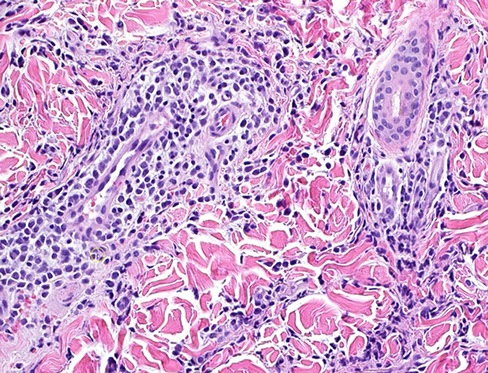

LyP type A

Lymphomatoid papulosis (LyP)

- a CD30-positive lymphophroliferative disorder

Rare, Indolent (self-healing) and chronic papulonodular skin dz c recurrent crops of pruritic papules at different stages of development that arises on the trunk and limbs; ~50 yo M, younger F

- histologically is a CD30+ proliferation of atypical T cells (is part of primary cutaneous CD30+ lymphoproliferatice disorders that includes Primary Cutaenous Anaplastic Large Cell Lymphoma [PC-ALCL] and borderline CD30+ lesions) - has many histologic mimics

- inc freq of prior, coexisting or subsequent lymphoproliferative disorders, usually mycosis fungoides or Hodgkin lymphoma

6 major subtypes:

Type A (MC, ~3/4): Hodgkin-like large atypical cells with intermixed mixed inflam infiltrates (neuts, lymphs, eos, histiocytes)

Type B: MF-like cerebriform cells c predominant epodermotrophic infiltrate

Type C: ALCL-like c large atypical cells and few other inflam cells (distinction from ALCL primarily clinical)

Type D: CD8+ cytotoxic T cell lymphoma-like c pagetoid infiltrate of epidermotrophic small to med-sized atypical CD8+ and CD30+ cells

Type E: Angiocentric infiltrates of small to med pleomorphic cells

Lyp with 6p23.3 rearrangement: Biphasic c small to med cerebriform cells and large atypical cells; usually seen in older adults

Micro: wedge-shaped infiltrate of T cells

IHC: (+) CD30 (CD30+ cells may be aberrant T cells) ,CD3 / 4

- neg ALK, CD8, CD56 (rare +)

DDx: Some immunoblasts, reactive T-cells, can be CD30+, scabies and arthropod bites can have a lot of CD30+ cells too

- Primary cutaneous anaplastic large cell lymphoma (PC-ALCL) can have lots of large ugly cells, the only way you would be able to differentiate is from IRF4 and the clinical history (if waxes and wanes, may consider LyP)

Dx: TCR rearrangement in 2/5 to 5/5 [1]

Px: excellent; although at inc risk secondary or nodal lymphoma such as MF, PC-ALCL and Hodkin lymphoma (up to 1/5)

- not known why there is spontaneous regression, but may be due to simultaneous expression of CD30 and CD95 (Fas) ligand

LyP - Scattered large cells with scattered smaller cells and neutrophils (mixed inflammatory background) wiht eos

LyP

LyP type C with diffuse sheets of CD30+ cells